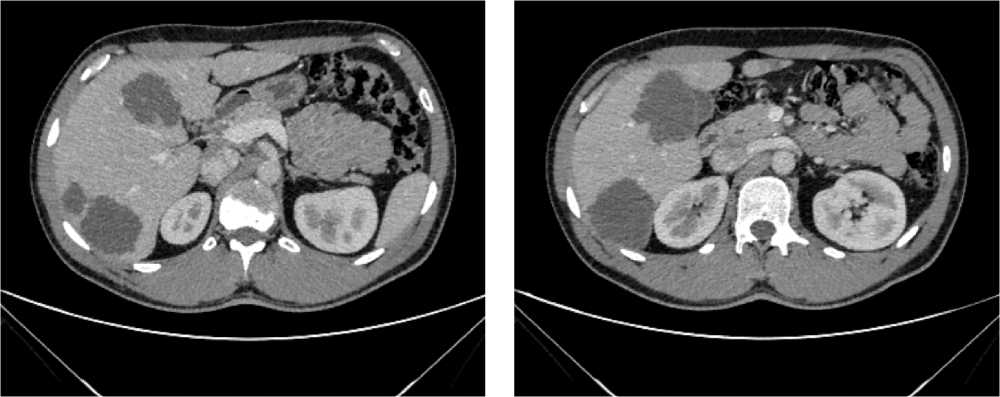

Выполнена компьютерная томография (КТ) органов грудной клетки, брюшной полости в июле 2019 г. Инфильтративных изменений в легких не обнаружено. Выявлено новообразование антрального отдела, малой кривизны и передней стенки желудка, распространяющееся на заднюю стенку, преимущественно на препилорический отдел. Имелись признаки локального перехода образования на большой сальник, гепатодуоденальную связку с периваскулярным ростом и признаками лимфоваскулярной инвазии. Многочисленные забрюшинные ЛУ сливались между собой в конгломераты размерами до 40 × 29 мм с частичным вовлечением почечных артерий. Также билобарно обнаружены немногочисленные очаговые образования в печени до 10 мм. Высказано подозрение на перитонеальный канцероматоз (рис. 3).

Рис. 3. Результаты компьютерной томографии органов брюшной полости у пациента 80 лет с диагнозом метастатический рак желудка с признаками микросателлитной нестабильности (июль 2019 г., до лечения)

Fig. 3. Results of a CT scan of the abdomen in an 80-year-old patient with metastatic MSI-H gastric cancer (July 2019, before treatment)

В результате обследования был установлен диагноз рака антрального отдела желудка (c)T4аN3вM1. По решению онкологического консилиума, учитывающего молекулярно-генетический профиль опухоли, а также возраст пациента, выраженность сопутствующей патологии (в анамнезе острое нарушение мозгового кровообращения (ОНМК), острый инфаркт миокарда (ОИМ), фибрилляция предсердий (ФП), постоянная форма), ограничивающей проведение ПХТ, была начата ИТ 1 линии пембролизумабом. С сентября 2019 г. по декабрь 2021 г. проведено 29 циклов ИТ 1 линии по схеме пембролизумаб в монорежиме с максимальным эффектом частичный регресс (рис. 4). Осложнений лечения не зарегистрировано.